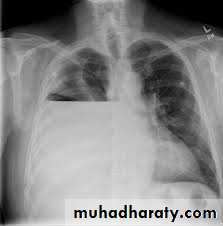

Differential Diagnosis for upper Abdominal Pain and Tenderness

Perforated Viscus, especially peptic ulcerErect CXR

ESRPneumonia

CXRDiabetic Ketoacidosis